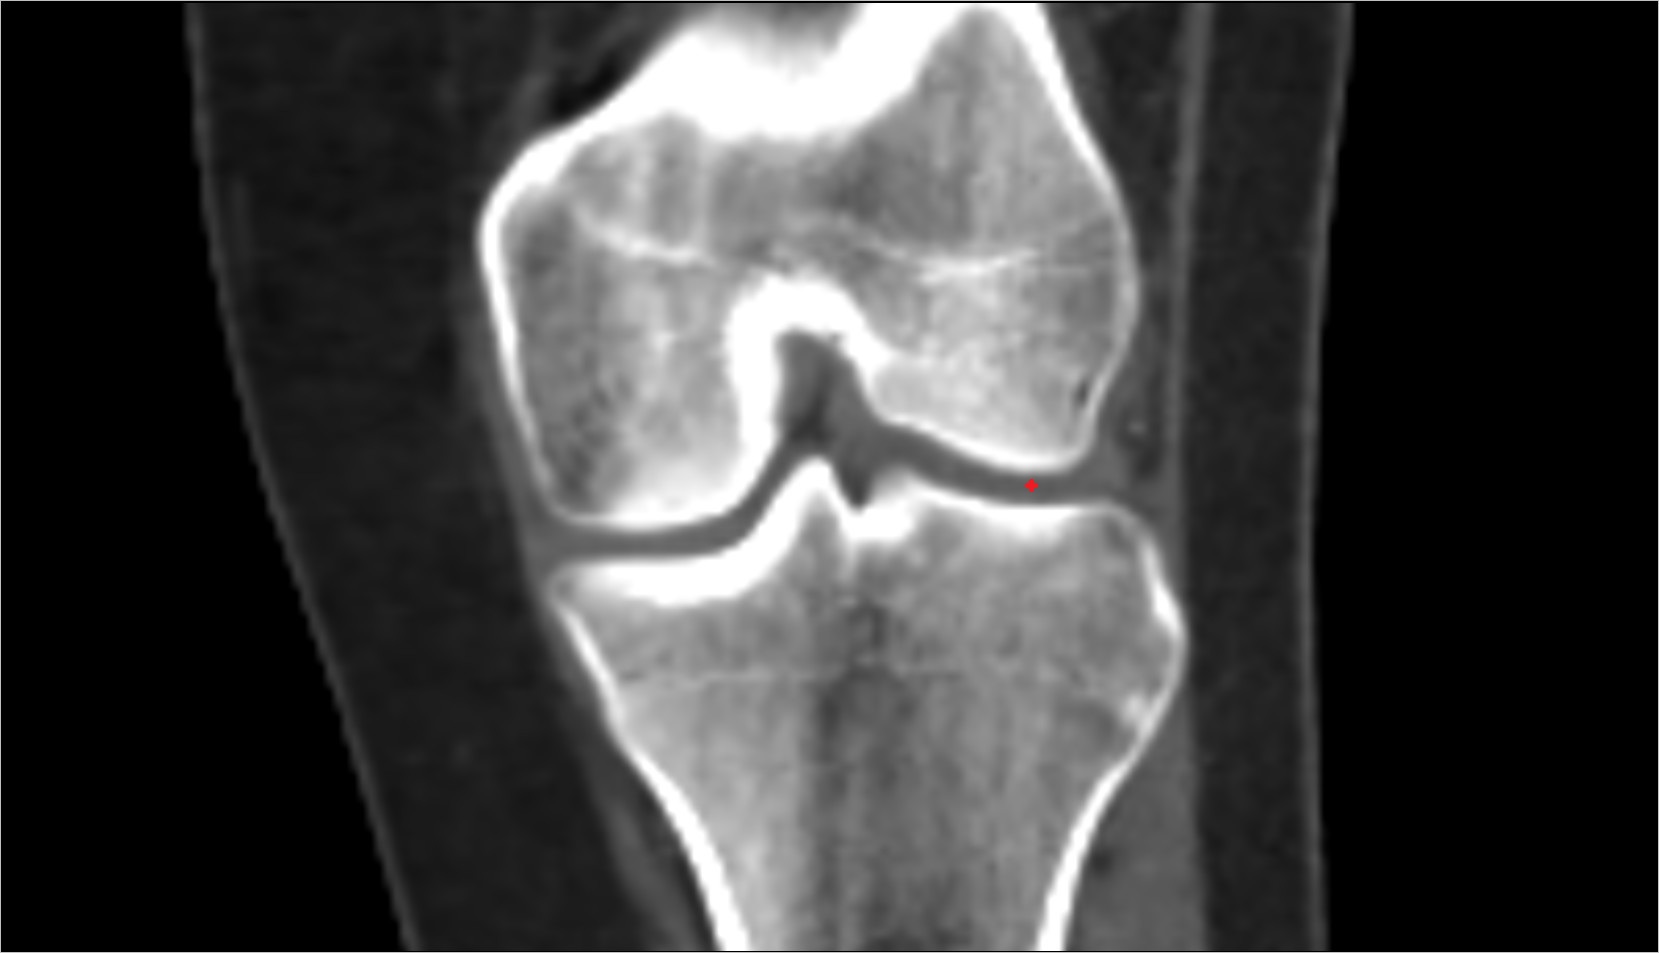

- Knee Joint

- Medial condyle of femur

- Lateral condyle of femur

- Femoral condyle articular cartilage

- Tibial condyle articular cartilage